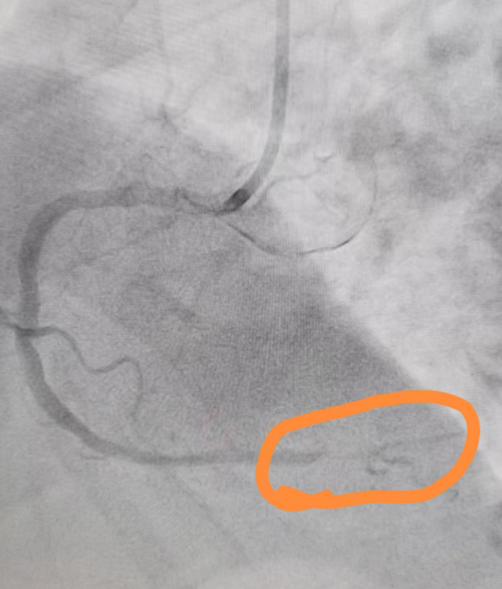

术中高效完成桡动脉穿刺,并即刻进行冠状动脉造影检查,影像学提示右冠状动脉远端完全闭塞。团队迅速评估病情,果断采用导丝技术成功通过闭塞病变段,随后使用预扩球囊对病变部位进行充分扩张,有效恢复血管管腔通畅性,在此基础上精准定位并成功植入支架一枚,实现右冠远端血运重建。术后造影显示血流恢复至TIMI 3级,手术顺利完成。

术前血管严重堵塞